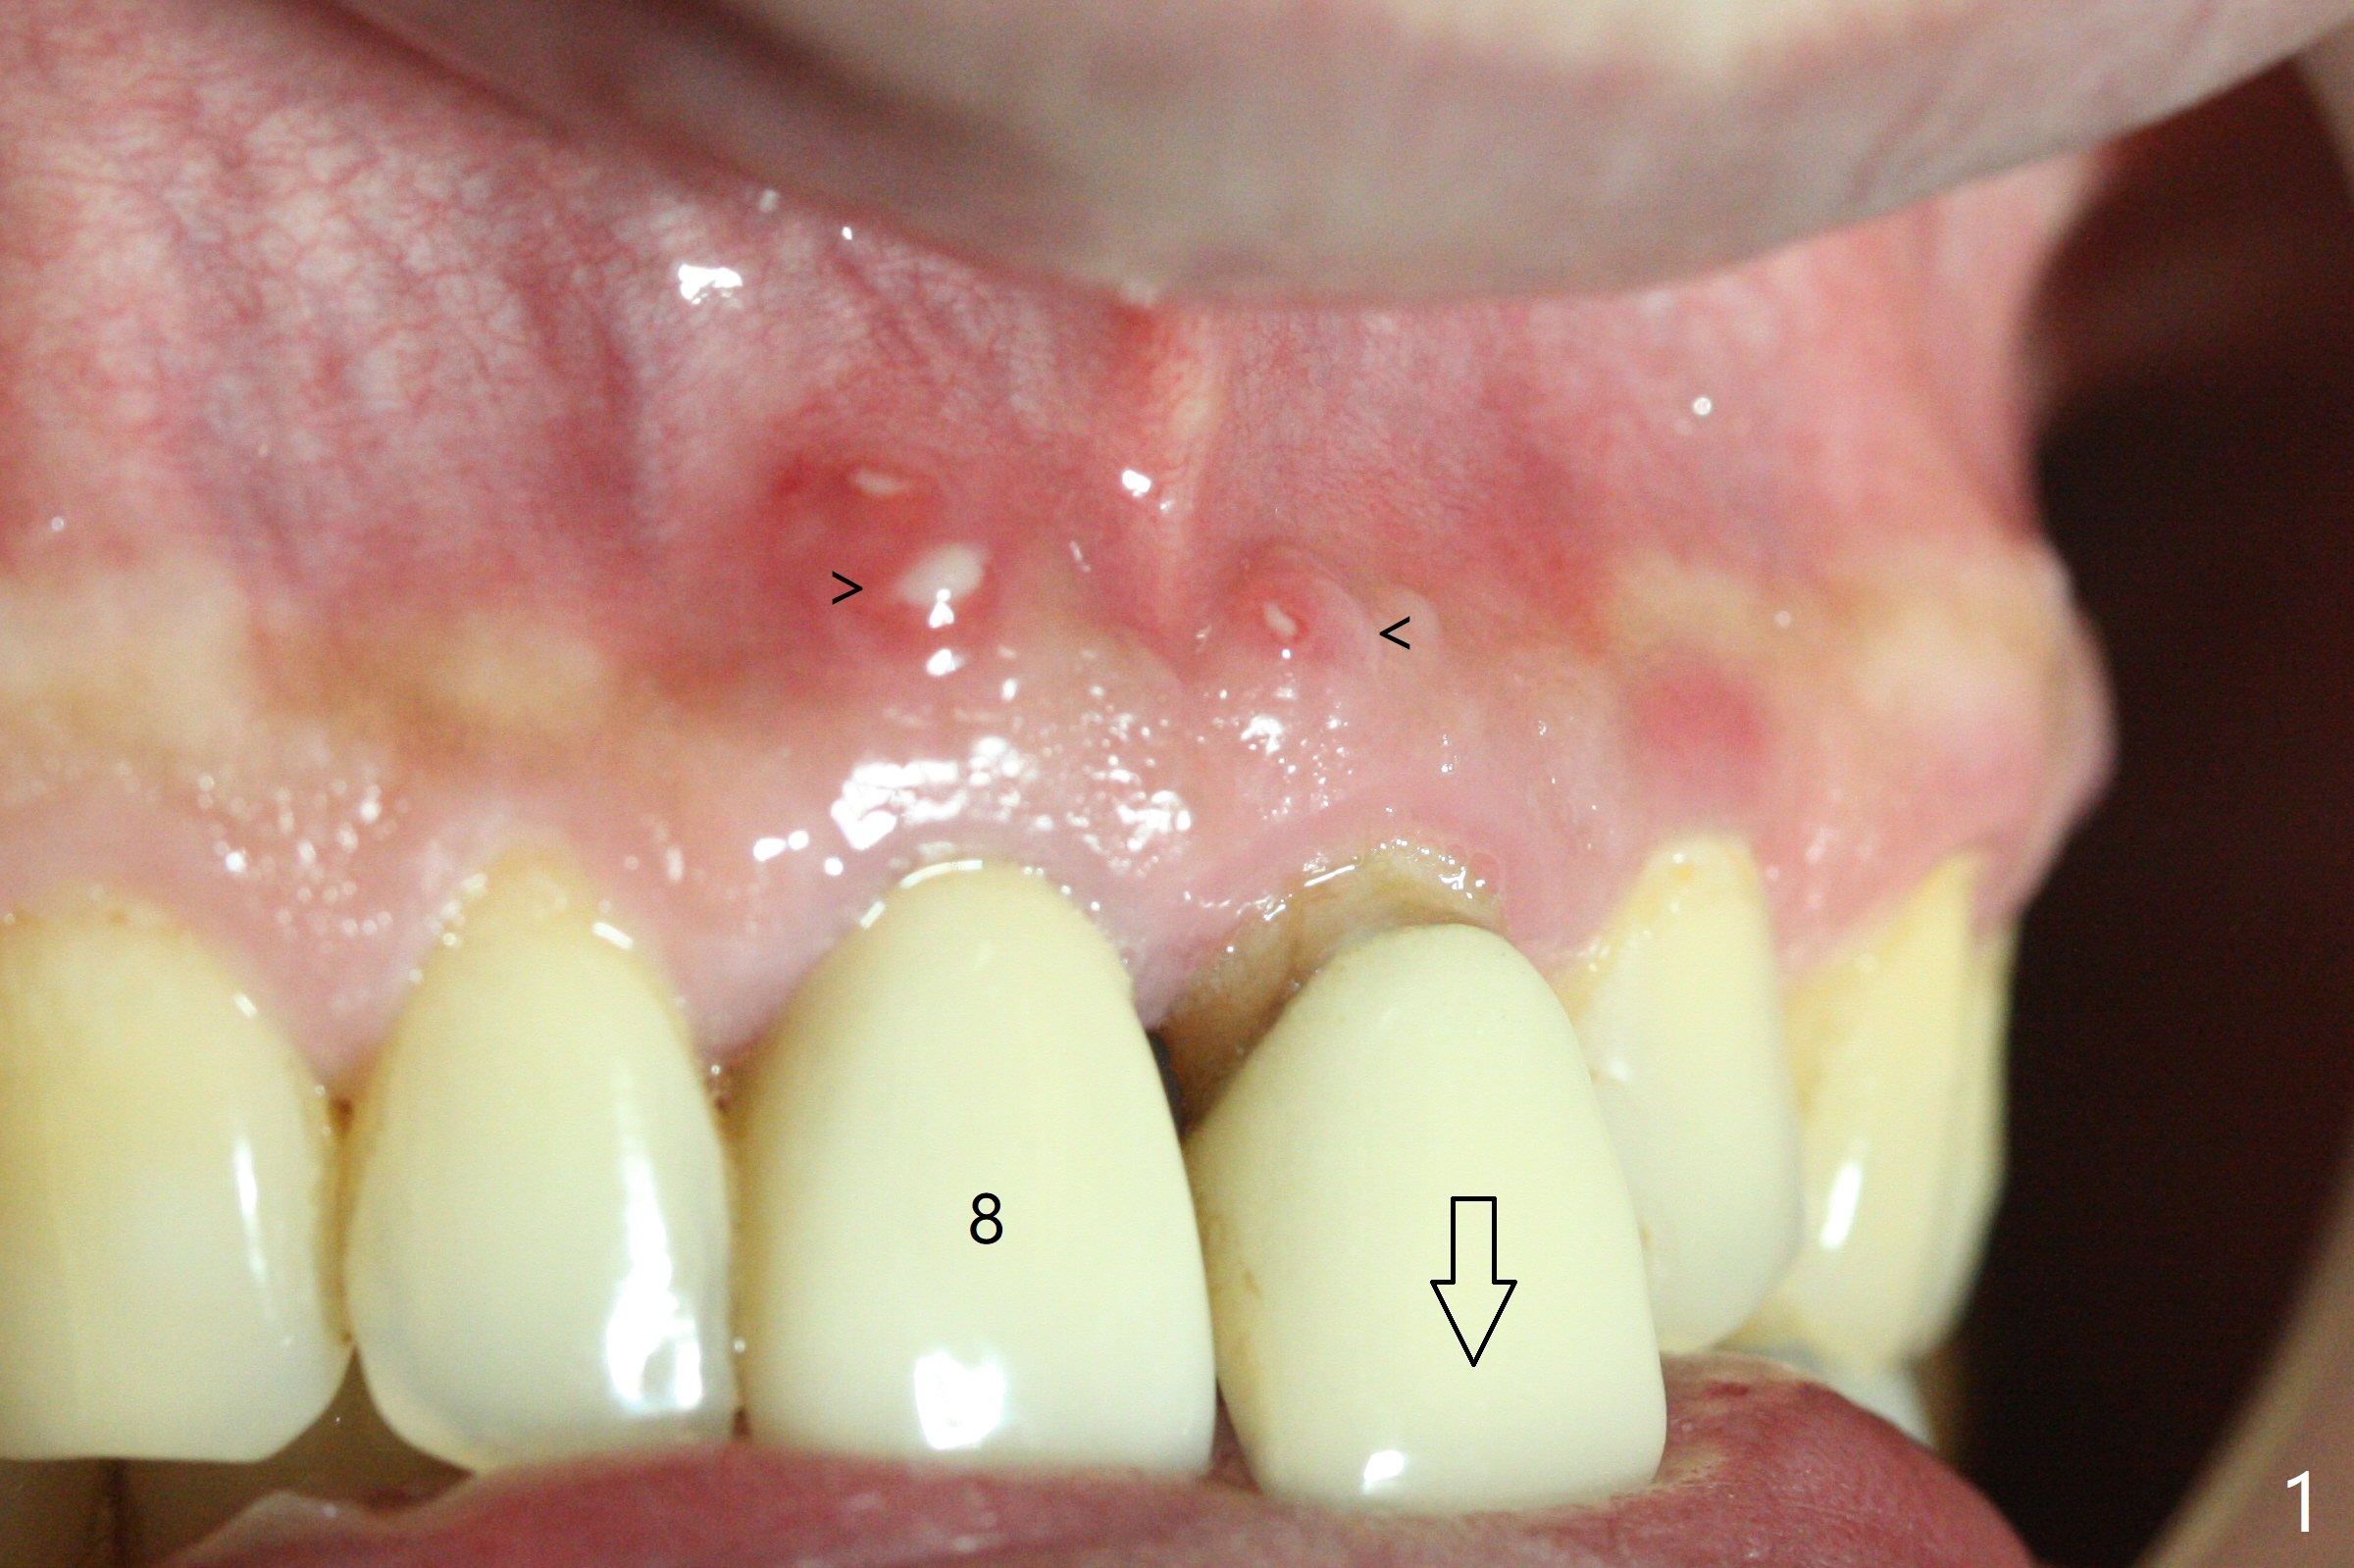

A 55-year-old man does not like the extruding tooth #9 (Fig.1,2). While there are fistulae associated with the two central incisors (arrowheads in Fig.1,2), bone loss appears to be apical at #8 and crestal at #9 (Fig.3 *). To avoid iatrogenic bone loss associated with two neighboring implants in the cosmetic zone, apicoectomy is to be performed at #8, while an immediate implant will be placed at #9 with guide at the same time (Fig.4). Furthermore there is missing or thin buccal plate at #8 (Fig.5 B).